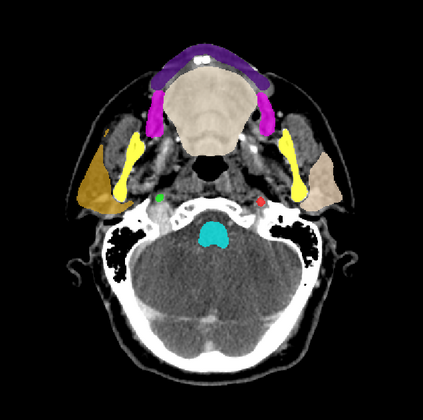

Organ at risk (OAR) segmentation is a critical process in radiotherapy treatment planning such as head and neck tumors. Nevertheless, in clinical practice, radiation oncologists predominantly perform OAR segmentations manually on CT scans. This manual process is highly time-consuming and expensive, limiting the number of patients who can receive timely radiotherapy. Additionally, CT scans offer lower soft-tissue contrast compared to MRI. Despite MRI providing superior soft-tissue visualization, its time-consuming nature makes it infeasible for real-time treatment planning. To address these challenges, we propose a method called SegReg, which utilizes Elastic Symmetric Normalization for registering MRI to perform OAR segmentation. SegReg outperforms the CT-only baseline by 16.78% in mDSC and 18.77% in mIoU, showing that it effectively combines the geometric accuracy of CT with the superior soft-tissue contrast of MRI, making accurate automated OAR segmentation for clinical practice become possible. See project website https://steve-zeyu-zhang.github.io/SegReg